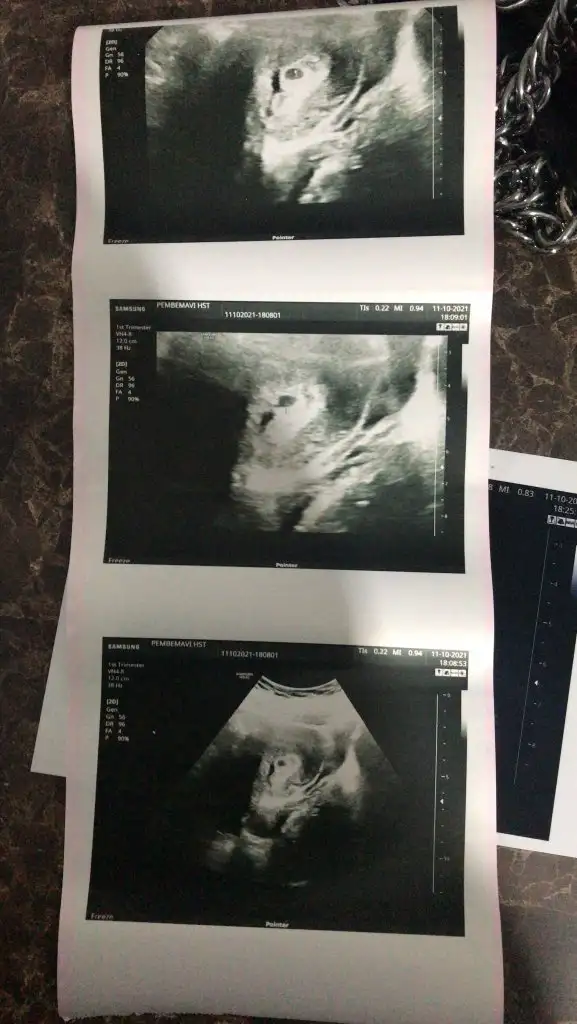

aynı şeyleri ilk hamileligimde bende yaşadım canım. hatta kanamayı gittiğim dr. görmedi ve iyi ki 1 hafta ara ile farklı bi dr. gittim o söyledi ve hemen progestana başladı. ilk 3 ay ara ara devam etti ama cok şükür gecti ve tabi sonrasında gebelik zehirlenmesi felan derken benim kuzum 2070g doğdu. neyse cok uzatmadanSelam kızlar bir tık içim buruk yazıyorum. Keseyi gördük Ama kesenin arkasında kan birikmesi varmış. Doktor bunun için ilaç verdi Protestan. Vajinadan almamı söyledi daha etkili oluyormuş o zaman. Kalp atışı duyana kadar alacağım. Düşük olma ihtimali var dedi. Ama çokta korkutarak söylemedi. Bütün risklerinden bahsetti. Sizde düşük olacağını zannetmiyorum ama riski var dedi. Genelde kese büyüdükçe kesenin arkasında ki kan gider dedi. Ya da vajinadan akar gider dedi. Kırmızı renkli kan görürsen hemen gel dedi sadece. Cumartesi günü tekrar kontrole gidicem. Bu köşedeki kan için. Kalp atışı içinde 2 hafta sonra çağırdı

Canım yolkdan falan hiç bahsetmedi. Karından keseyi görünce hemen arkasında ki kanamadan bahsetti sürekli. Korkulacak bir şey yok tedbir alalım dedi ama bilmiyorum.Canım yolk salc da görüldümü ayrıca şunu söyleyim dışarıya aktif kanaman yoksa bu güzel bişey çünkü içerdeki o kanama alanında vitamin falan varmış ve kese büyüdükçe o kandan vitamini alıp kanama alanını küçültüyomuş progestanı düzenli kullan Allah ona ömür vermişse hiç bişey olmaz

Merhabalar canım bakıyorum ama ev ödev iş yazamadım. Hiç korkma ben kızımda da aynı şeyi duymuştum ve 27 haftaya dek progestan kullanmıştım Rabbimin izniyle bu gruptaki tüm anneler sağlıkla kucaklayacağız inşaallah gönlünü ferah tut karnını tut bolca ihlas ya safi oku moral en önemli şey. Biz seninle aynı sat da batda. Ben geçen hafta kese gördüm 15 gün sonra gel dedi beklemedeyim tedirgin ve heyecan içindeyim ikinci gebelik olsa da . Öpüyorum çokça içini ferah tut masana oturunca tak kulağına aç youtube ver hareketli şarkıları kendine gelirsin bende öyle yapıyorumsweetgirlcandy canım ben de keseyi görünce yazıcam demiştim. kanama alanı var ama olsun içimi ferah tutmak istiyorum ben.

keseyi 5+0 da gördüm 4+0 da olabilir ondan tam emin değilim doktor net bir şey söylemedi. sadece 1 hafta gerisin geç döllenme olmuş dedi. son bat tarihim 31 ağustostu. ordan hesaplarsam 6 hafta olması lazım aslında ama 1 hafta geri diyince 5 haftaya denk geliyor sanırım :)